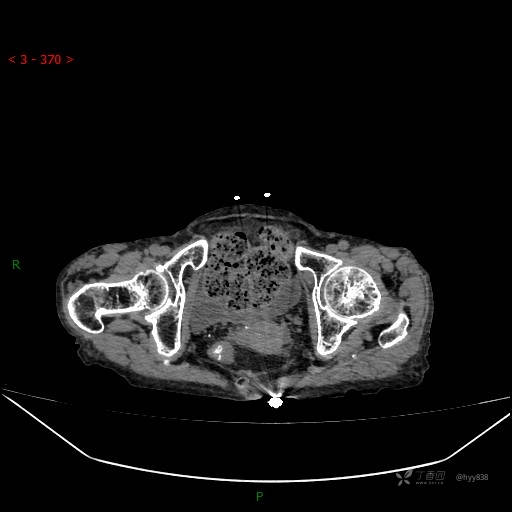

夜班急诊经典病例分享。老年女性,突发腹痛就诊,请讨论……结果公布~

主诉 :腹痛14小时

现病史: 家属诉患者于14小时前出现腹痛,伴有肛门停止排气排便,不伴有畏寒、发热、恶心呕吐、腹泻等不适,患者家属为求进一步治疗,就诊于我院急诊科,门诊以腹痛待查收入院, 起病以来,患者精神、睡眠差,进食少,小便正常,大便未解,近期体力、体重无明显下降。

腹部CT平扫